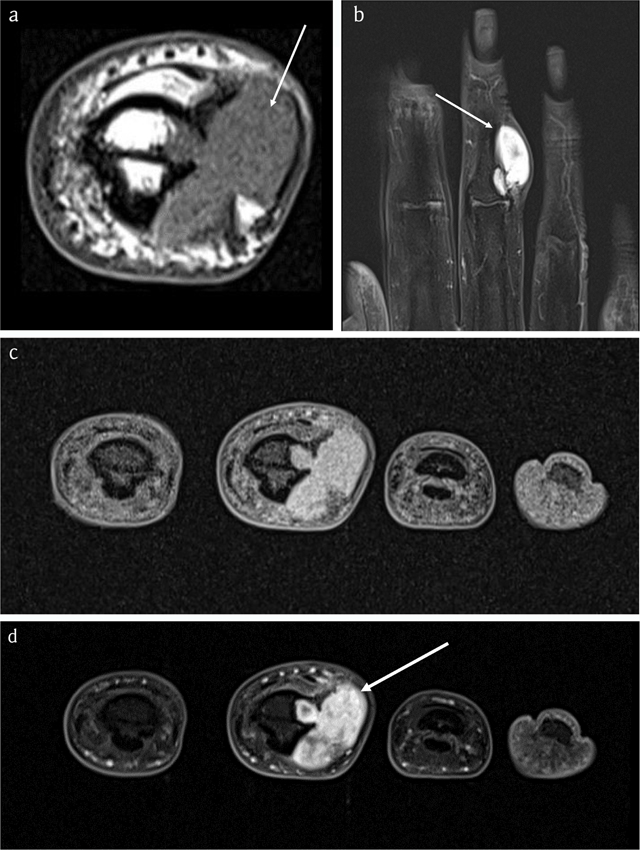

Figure 2

Case 1 – MRI. Sagittal T1-WI (3 adjacent slices) (a). Sagittal fat-suppressed (FS) T2-WI (2 adjacent slices) (b). Axial FS T1-WI (c). Axial FS T1-WI after intravenous administration of gadolinium contrast (d). The lesion is isointense to muscle on T1-WI (arrows in a) and hyperintense on FS T2-WI (arrows in b) and enhances peripherally, in keeping with chondroid matrix (arrow in d).